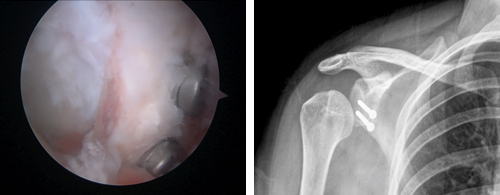

O labrum glenóide é uma estrutura fibrocartilaginea semelhante a um menisco que aumenta o contacto com a cabeça umeral estabilizando a articulação.

A Coifa dos Rotadores funciona como uma convergência de tendões, em redor da cabeça do úmero. Os tendões dos quatro músculos unem-se com a cápsula articular da articulação glenoumeral.